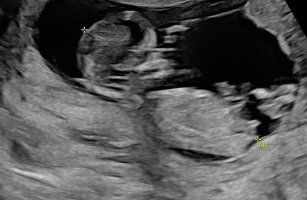

Gjetter guttNoen som vil gjette kjønn? 13+2. Jeg spurte jordmor, hun ville ikke svare fordi hun mente det ikke var tydelig nok. Synes det ene bildet ser ut som jente, og på det andre ser det ut som en gutt

Jeg tipper og gutt. Skjønner hva du mener, at det ser litt flatere ut på det ene bildet, men likevel, hvis du følger kurven til ryggraden, så er vinkelen kanskje liiiitt for mye til å være jente?Noen som vil gjette kjønn? 13+2. Jeg spurte jordmor, hun ville ikke svare fordi hun mente det ikke var tydelig nok. Synes det ene bildet ser ut som jente, og på det andre ser det ut som en gutt

Jeg syntes dette ser ut som en jente, for på bilde to ser det ut som deler av rumpa ikke er i bilde så da ser det ut som nuben er mindre parallell enn det den er.Noen som vil gjette kjønn? 13+2. Jeg spurte jordmor, hun ville ikke svare fordi hun mente det ikke var tydelig nok. Synes det ene bildet ser ut som jente, og på det andre ser det ut som en gutt

Du skal følge kurven ut mot rumpa, så den er parallell.Jeg tipper og gutt. Skjønner hva du mener, at det ser litt flatere ut på det ene bildet, men likevel, hvis du følger kurven til ryggraden, så er vinkelen kanskje liiiitt for mye til å være jente?

Det er 100% en jente. Du har to hvite streker godt synlig. På min private ultralyd så forklarte legen at man så kun disse to strekene på jentebarn. Grunnen til at du tror det er gutt på bildet 2 er stillingen til barnet. Hun sitter og derfor peker nub litt opp.Noen som vil gjette kjønn? 13+2. Jeg spurte jordmor, hun ville ikke svare fordi hun mente det ikke var tydelig nok. Synes det ene bildet ser ut som jente, og på det andre ser det ut som en gutt